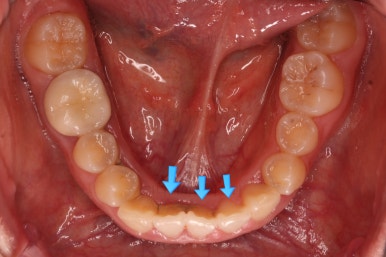

문제의 시작은 바로 아래 앞니였어요.

맨 아래 오른쪽 사진에 화살표를 보시면 앞니가 4개여야 하는데 3개 밖에 없네요.

특히 아래 앞니는 1개 혹은 2개가 없는 결손치아인 환자분이 상당히 많습니다.

치아가 없으면? = 임플란트! 라고 생각하실 수 있는데 치아교정을 통해서 다양한 방법을 사용할 수 있습니다.

아래 앞니 3개인 채로 마무리를 하기도 하고 4개처럼 보이게끔 마무리를 하기도 합니다.

이번 환자분의 경우는 치아 크기와 비율, 교합 등을 전반적으로 고려해서 아래 앞니가 마치 4개인 것처럼 마무리를 하기로 했습니다.

뒤쪽 치아를 차례차례 끌고 당겨와서 앞니를 대신하는거죠.

물론 기간은 많이 걸리나 현재로서는 가장 합리적인 방법으로 판단했습니다.